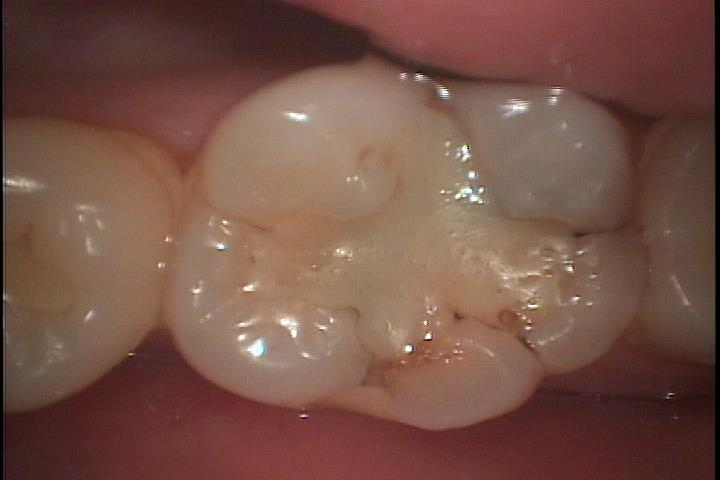

症例です

歯を上から眺めて見ます。

中心部にコンポジットレジンが充填され四方にクラックが入っています。

少し角度を変えて側面から見るとクラックに色素が沈着し黒くなっているのがわかります。虫歯になっている可能性が高いです。